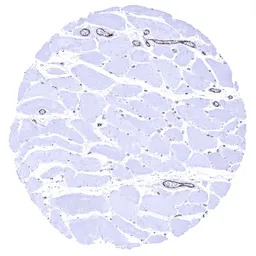

IHC-P analysis of human skeletal muscle tissue section using GTX04412 VWF antibody [MSVA-521R] HistoMAX.

In skeletal muscle endothelial VWF immunostaining is strong in postcapillary venules and somewhat weaker in capillaries.